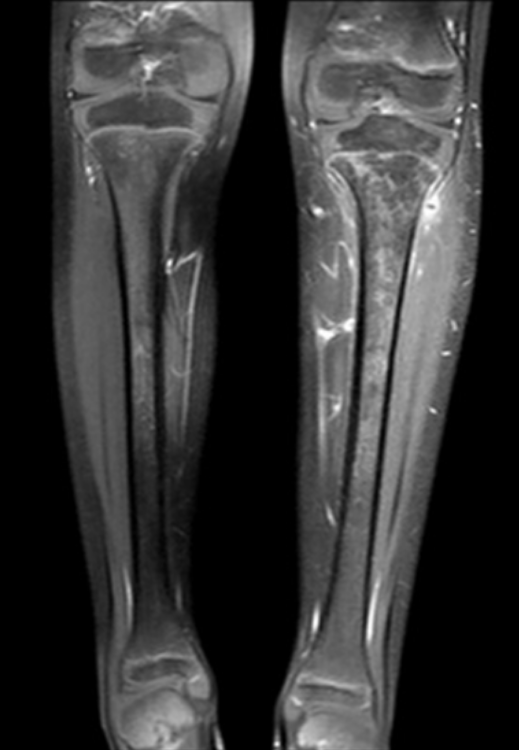

3

Q

What are the present soft tissue findings?

A

• Soft tissue emphysema

• Sequestrum

• Swelling

osteomyelitis